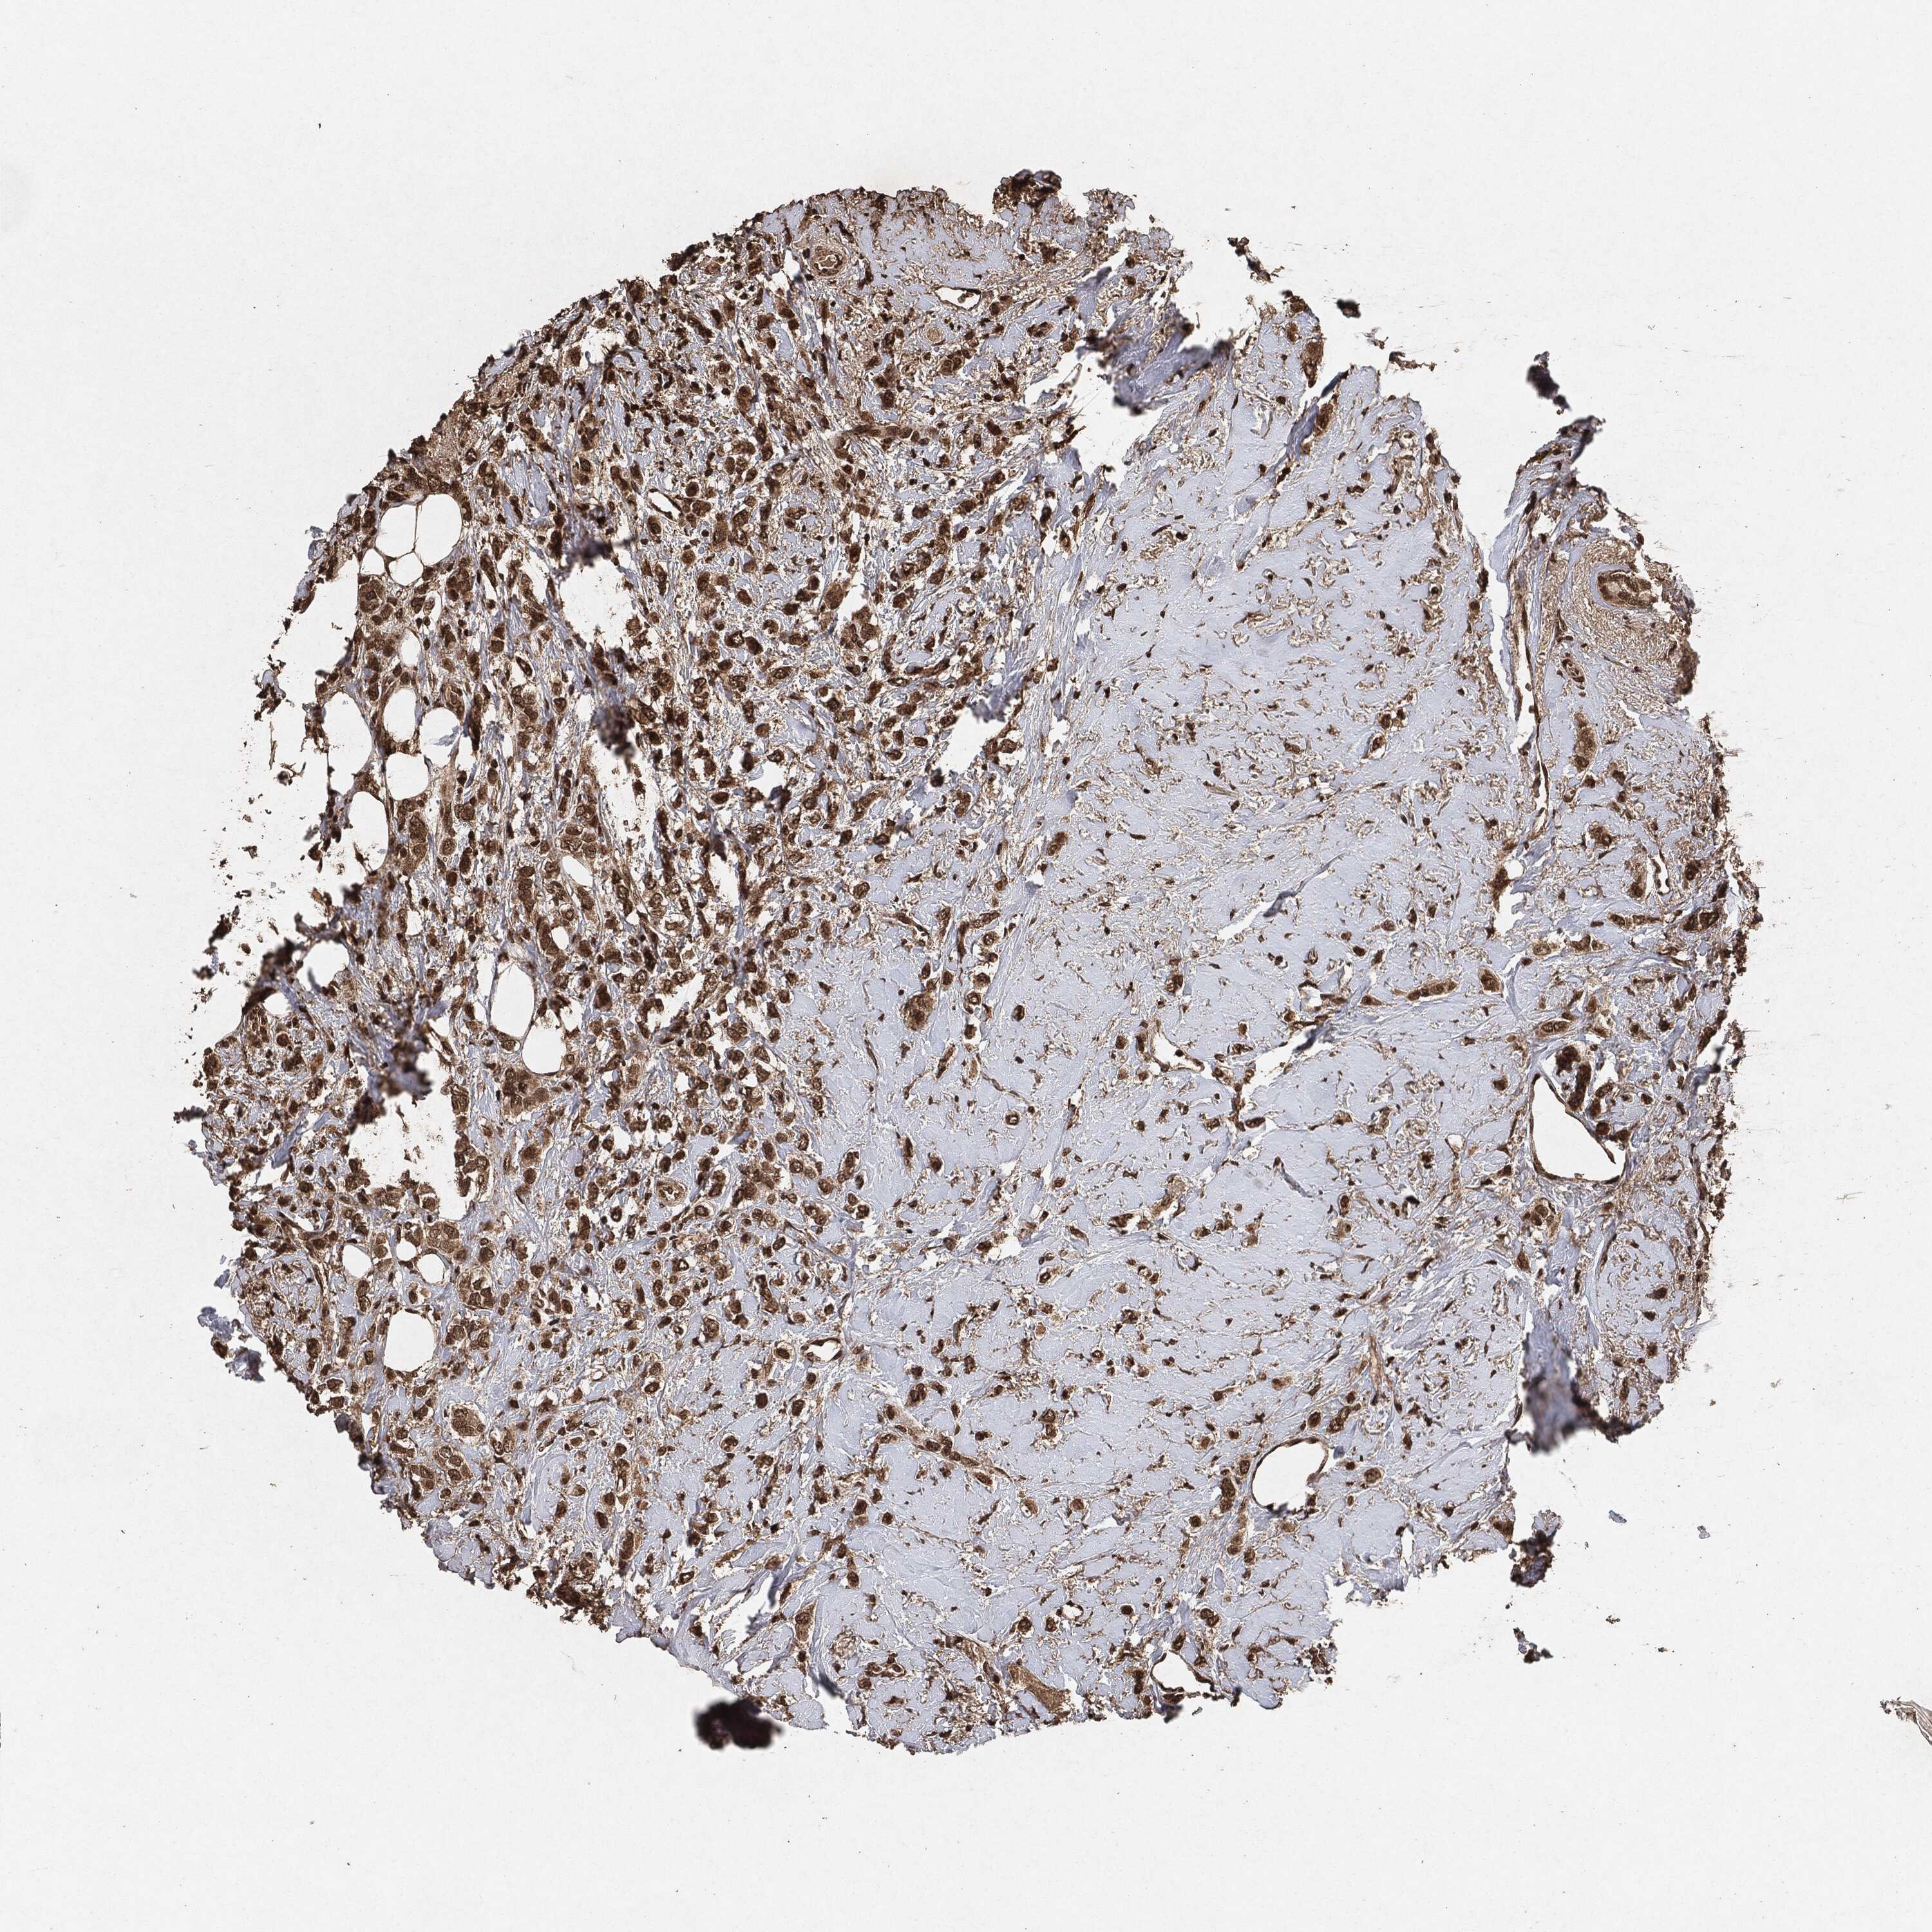

BRCA TCGA BRCA VALIDATION PROTEIN EXPRESSION